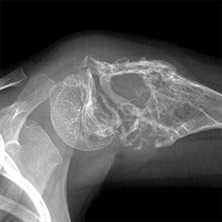

(Справа) МРТ Т2ВИ, сагиттальный срез: в этом же случае определяется очень низкая ИС от костей плечевого пояса. Плечо на противоположной стороне характеризуется схожим сигналом. Неудивительно, что этот пациент страдает талассемией; низкая ИС является проявлением как гиперплазии костного мозга, так и отложения гемосидерина. (Слева) КТ, костное окно, корональный срез: у мужчины 37 лет с талассемией определяется диффузная остеопения вплоть до точечного лизиса костной ткани. Оставшиеся трабекулы утолщены, эндостальная кортикальная пластинка истончена. Другим признаком, говорящим о наличии талассемии, является спленомегалия.

(Справа) КТ, корональный срез: у этого же пациента определяется как спленомегалия, так и утолщение трабекул. (Слева) КТ, аксиальный срез: у этого же пациента определяются оставшиеся трабекулы тела позвонка в виде рисунка в «мелкий горошек». Околопозвоночные мягкотканные объемные образования соответствуют внекостномозговым очагам кроветворения, также характерным для талассемии.